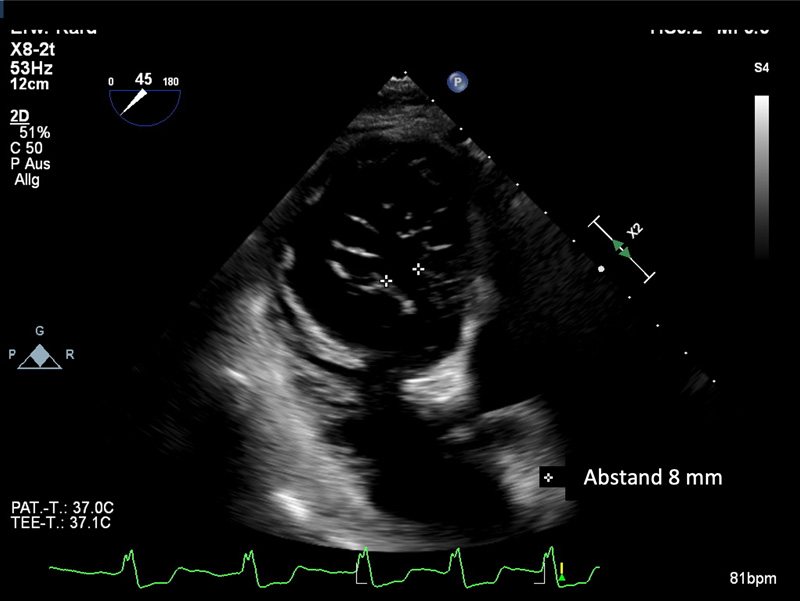

Ausmaß des Koaptationsdefektes vor Therapie mit hochdosierten intravenösen Schleifendiuretika (Furosemid 240 mg/d für 2 Tage vor T-TEER).

Ausmaß der Anpassungslücke nach hochdosierter IV-Schleifendiuretika (Furosemid 240 mg/d für 2 Tage) vor T-TEER

Der Koaptationsdefekt wurde durch den Annuloplastie-Effekt des 1.TriClips auf 8mm reduziert

Im Gegensatz zu anderen Herzklappenerkrankungen, bei denen es nur drei Schweregrade gibt, wird der Schweregrad der TR derzeit in fünf verschiedene Schweregrade unterteilt. In diesem Fall hat der von Dr. Osteresch vorgestellte Patient eine torrentiale TR mit einer Lücke von 11-12 mm zum Zeitpunkt der Erstdiagnose. Es gibt gute Belege dafür, dass Patienten mit einer so großen Lücke nicht wirksam mit T-TEER behandelt werden können. Besler et al. zeigten, dass eine geringere Lückengröße ein unabhängiger Prädiktor für den Behandlungserfolg ist6. Die Schlüsselfrage ist jedoch, ob sich der Patient zum Zeitpunkt der Echokardiographie bereits in einer effektiv rekompensierten Situation befindet. In vielen Fällen ist es hilfreich und effektiv, ein paar Tage lang intensive Diuretika zu verabreichen und dann ein neues Echo durchzuführen. Es besteht eine hohe Wahrscheinlichkeit, die Lücke zu verringern und den Patienten in eine Situation zu bringen, in der T-TEER eine gute Behandlungsoption darstellt. Dies wurde auch im vorliegenden Fall gut beobachtet, wobei der Spalt von 11-12 mm auf 8 mm reduziert wurde.